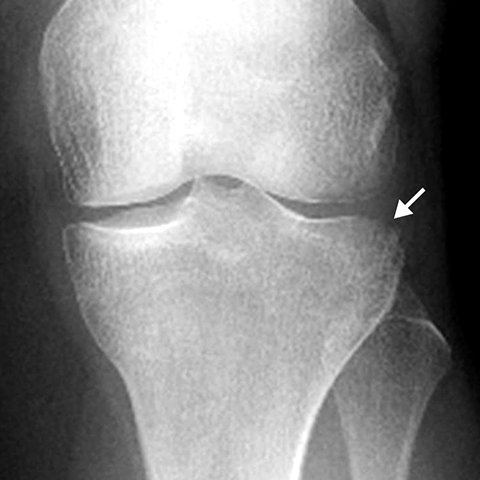

Plateau Fracture [1 of 2]